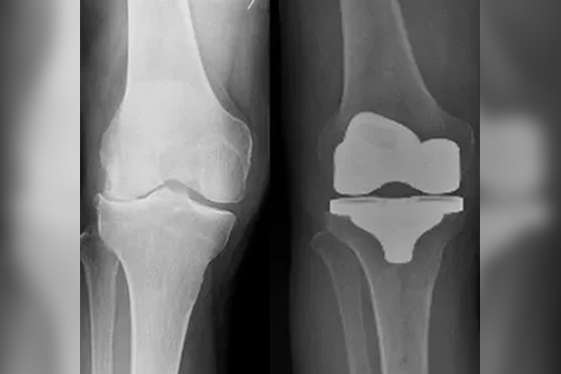

Total Knee Replacement (TKR)

Our minimally invasive and fast-track TKR can help you get back on your feet early after surgery. We have special expertise in complex knee replacements like severe deformities, bone defects, obese patients, arthritis with old fractures or previous surgeries, and retained metal implants like rod, plate, and screws. Total knee replacement is useful in the treatment of osteoarthritis, rheumatoid arthritis, inflammatory arthritis, post-traumatic arthritis, osteonecrosis, etc. The use of advanced prosthetic implants for TKR can help provide best and long-lasting results after knee replacement.